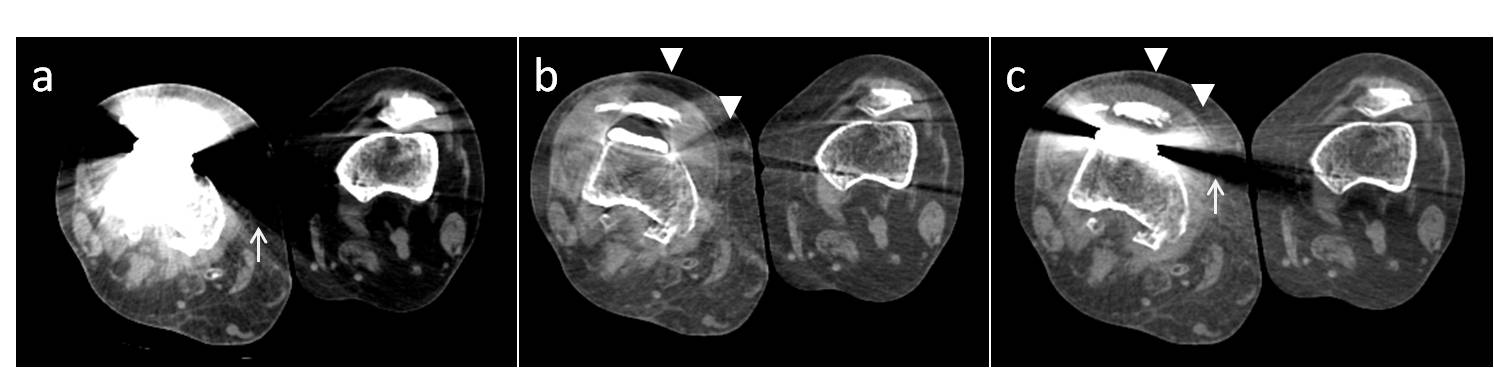

6. Wang Y, Qian B, Li B, Qin G, Zhou Z, Qiu Y, Sun X, Zhu B. Metal artifacts reduction using monochromatic images from spectral ct: Evaluation of pedicle screws in patients with scoliosis. European journal of radiology. 2013;82:e360-366

17. Guggenberger R, Winklhofer S, Osterhoff G, Wanner GA, Fortunati M, Andreisek G, Alkadhi H, Stolzmann P. Metallic artefact reduction with monoenergetic dual-energy ct: Systematic ex vivo evaluation of posterior spinal fusion implants from various vendors and different spine levels. European radiology. 2012;22:2357-2364